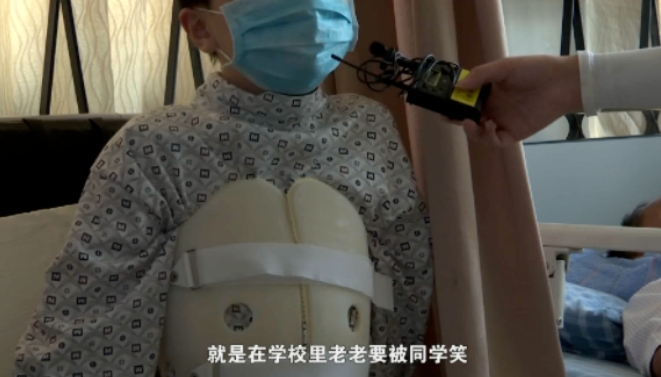

首先是影响孩子的身形。 比如,脊柱侧弯可能导致孩子背部不平,胸廓畸形,长短腿等肉眼可见的变化。这些外形的变化会直接导致孩子自卑。尤其半大不小的孩子,爱玩爱闹,但也容易失去分寸。脊椎侧弯的孩子,就很可能会成为被同学嘲笑、甚至被同学排挤的对象。其次,影响身体健康。